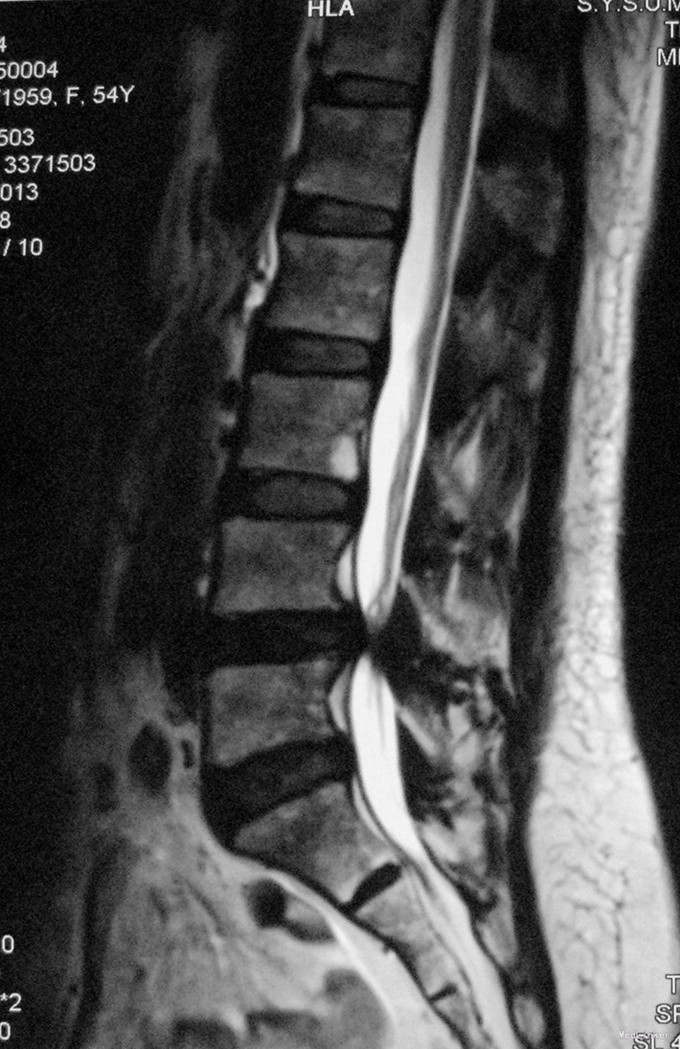

主诉:诉腰痛并双下肢间歇性跛行半年余。 病史:患者诉半年前无明显诱因出现腰部疼痛,呈酸胀感,起床、弯腰活动时为甚。伴双下肢间歇性跛行,步行不能超过200米,卧位休息后可缓解,无伴双下肢肿胀、发热等不适。到当地医院行MRI影像学检查,考虑腰4/5椎管狭窄症。现为进一步诊治收入我科。患者起病以来,无发热,无咳嗽咳痰,无胸闷气促,无腹胀腹痛,无尿频尿急。精神胃纳可,睡眠可,大小便正常。

查体:脊柱生理弯曲存在,腰椎活动受限,L4/L5棘突压痛叩痛,叩击痛。双侧直腿抬高试验(-)。双下肢皮肤感觉正常,双侧髂腰肌、股四头肌、双侧胫前肌、踇背伸肌肌力Ⅳ级,腹壁反射、肛门反射正常,两侧膝正常,双侧踝反射未引出。双侧Babinski征(-),双侧皮温及色泽正常,双侧足背动脉搏动良好。 辅助检查:X光片示:动力位片显示腰椎4/5椎间失稳。MRI检查显示:腰4/5椎间盘突出,黄韧带肥厚致椎管狭窄,相应节段硬膜囊受压改变。

诊断:腰4/5椎管狭窄并失稳症。 治疗:给予行后路腰4/5右侧椎板间开窗减压椎间盘摘除并肥厚黄韧带切除+棘突间wallis固定术。

随访示患者腰痛及双下肢跛行症状明显缓解。 讨论:该例患者临床症状主要为腰痛并间歇性跛行,椎间盘突出合并黄韧带肥厚致椎管狭窄,且存在轻度失稳,故给予椎管减压并棘突间wallis动态固定。术后效果满意。